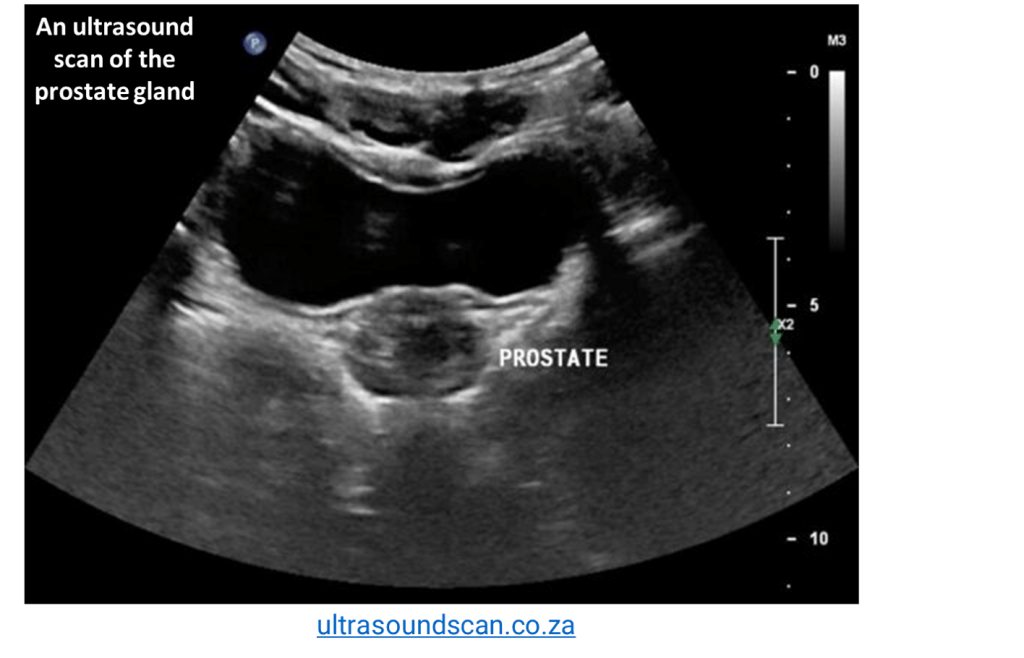

The Role Of Prostate Gland

What is the structure and function of the prostate gland?